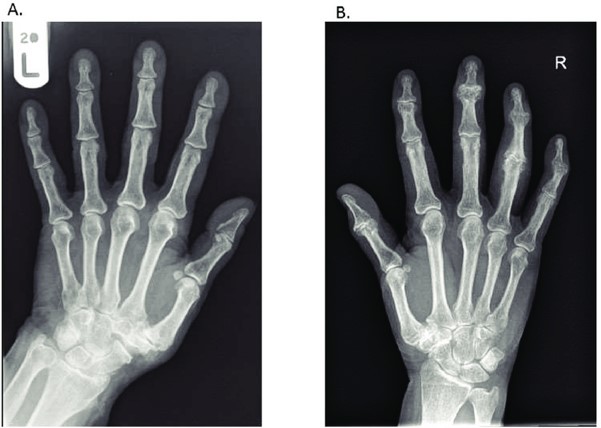

X-rays or other imaging can help confirm the diagnosis of osteoarthritis however the appearance of the disease on x-ray does not always correlate to symptoms severity.

Photo source: https://www.researchgate.net/figure/Plain-radiographic-changes-in-hand-osteoarthritis-due-to-thumb-first-carpometacarpal_fig1_328940288